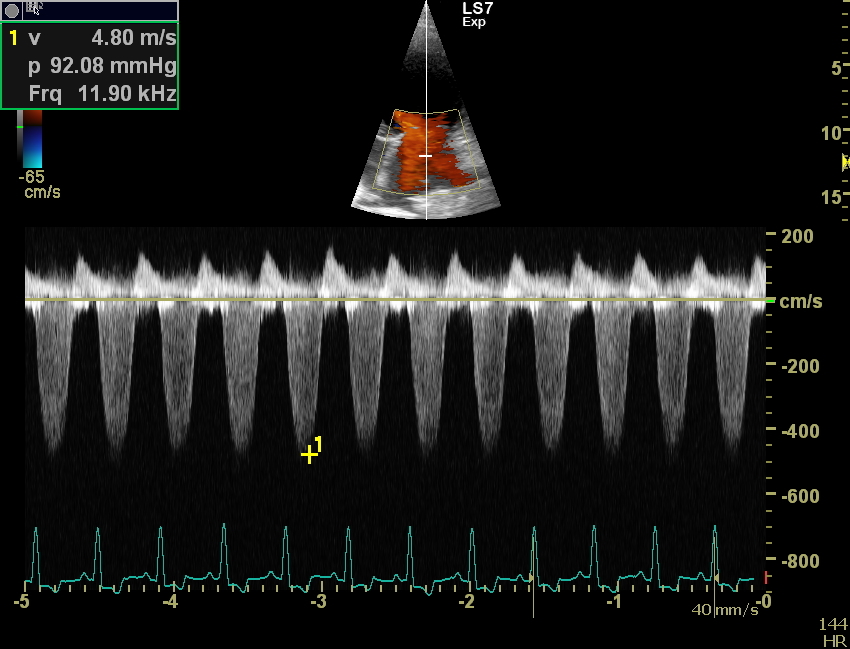

Weitergehend haben wir dann eine Herzultraschalluntersuchung durchgeführt um weitere Informationen über die zugrundeliegende Erkrankung zu bekommen. Auch in der Echokardiografie stellte sich das Herz deutlich zu groß da. Die linke Hauptkammer und der linke Vorhof sind massiv volumenüberladen, also mit zu viel Blut gefüllt. Durch die starke Blutfülle im Herzen hat sich auch der Klappenapparat der Mitralklappe aufgedehnt, sodass dieses Rückschlagsventil zwischen der linken Kammer und dem linken Vorhof nicht mehr richtig abdichtet. Resultat ist eine Mitralklappeninsuffizienz, die bei jedem Herzschlag etwas Blut in den linken Vorhof zurückfließen lässt. Der linke Vorhof wird, wie hier bei Faust sehr groß und das Blut staut in den Lungenkreislauf zurück, es entsteht ein Lungenödem. Vereinfacht gesagt Faust hat „Wasser auf der Lunge“, eine weitere wichtige Ursache für Husten bei unseren herzkranken Hunden. Die Herzmuskulatur bei Faust ist eher dünn und die Pumpkraft (Kontraktilität) der Herzmuskulatur ist sehr schwach.

Daraus leitet sich die Diagnose ab: Faust hat eine dilatative Cardiomyopathie, DCM.